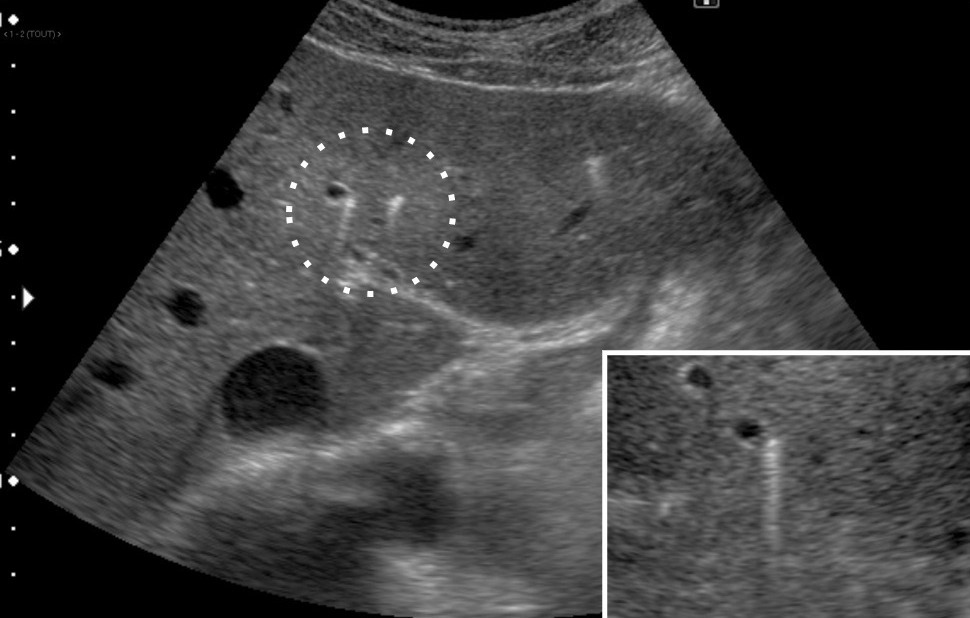

L’échographie hépatique est l’examen clé pour le diagnostic de syndrome LPAC. Celle-ci met typiquement en évidence les signes d’une microlithiase intrahépatique sous la forme d’images en « queue de comète » (échos de répétition liés à la vibration des microcristaux sous le faisceau d’ultrasons), de micro-­spots ou de « boue biliaire » (sludge) le long des canaux intrahépatiques (fig. 1A). Ces signes sont parfois difficilement identifiables, notamment en situation non sensibilisée et pour un opérateur non entraîné. Le principal diagnostic différentiel est représenté par les microhamartomes (ou complexes de von Meyenburg) qui peuvent parfois se présenter sous la forme d’artéfacts en queue de comète.9 Une échographie normale standard n’élimine pas le diag­nostic et il peut être nécessaire de répéter l’examen par un radiologue expérimenté et formé à la sémio­logie du syndrome LPAC. Moins fréquemment (5 à 10 % des cas), le syndrome LPAC peut se présenter sous la forme de vrais calculs (macrolithiases) intra- ou extrahépatiques (fig. 1B).4 Une lithiase vésiculaire n’est observée que chez un tiers des patients atteints de syndrome LPAC.